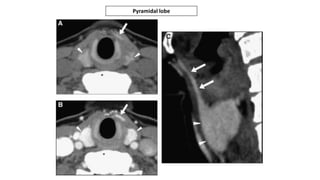

• #25 Contrast-enhanced computed tomography study of a patient with an infrahyoid ectopia of the thyroid gland shown by the arrows in all images. In (B), there is thyroid tissue not attached to the main ectopic glandular tissue, demonstrating the potential for all migrational abnormalities of the thyroid gland to result in disconnected lateral ectopic tissue (arrowheads). In (C), there are multiple small cysts within the ectopic tissue, suggesting that such ectopic tissue can develop abnormalities that might occur in normally positioned thyroid tissue (arrowheads).